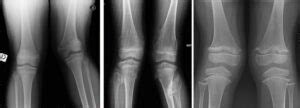

Knock knees , medically referred to as genu valgum , is a condition where a person’s knees angle inward, touching or even overlapping each other, while the ankles remain separated. Picture this: when standing with your feet together, there’s a noticeable gap between your ankles, and your knees are practically bumping into each other. It’s like your knees are giving each other a friendly (or not-so-friendly) hug! This can affect both children and adults, although it’s more common in children as they grow. It’s often a normal part of development in young children and usually corrects itself as they get older. However, in some cases, it can persist or develop later in life. This condition isn’t just about looks; it can impact your gait (the way you walk), how your joints function, and even the types of activities you can comfortably engage in. If you’re concerned about knock knees , it’s always best to consult with a healthcare professional to get an accurate diagnosis and understand any potential treatments or management strategies that might be suitable for you.

Genu valgum is more than just a cosmetic issue; it reflects an alignment problem in the lower extremities. The angle of the knees can affect the distribution of weight, potentially leading to increased stress on the inner parts of the knees and ankles. Over time, this can increase the risk of developing osteoarthritis or experiencing pain during activities that involve weight-bearing. The condition’s severity varies greatly from person to person. Some individuals might have a slight inward angle that doesn’t cause any problems, while others might experience significant pain and mobility limitations. Understanding the underlying causes is crucial for appropriate treatment and management. Factors such as genetics, nutrition, and underlying medical conditions can play a role. For example, conditions like rickets, caused by vitamin D deficiency, can lead to bone deformities, including knock knees . Similarly, injuries to the growth plates around the knee can also contribute to the condition. In any case, early detection and intervention can significantly impact the long-term prognosis. This might involve exercises, braces, or, in severe cases, surgical interventions to correct the alignment of the legs. Therefore, if you suspect that you or someone you know has knock knees , consult with a healthcare provider to determine the best course of action. This will help maintain good overall health and well-being.